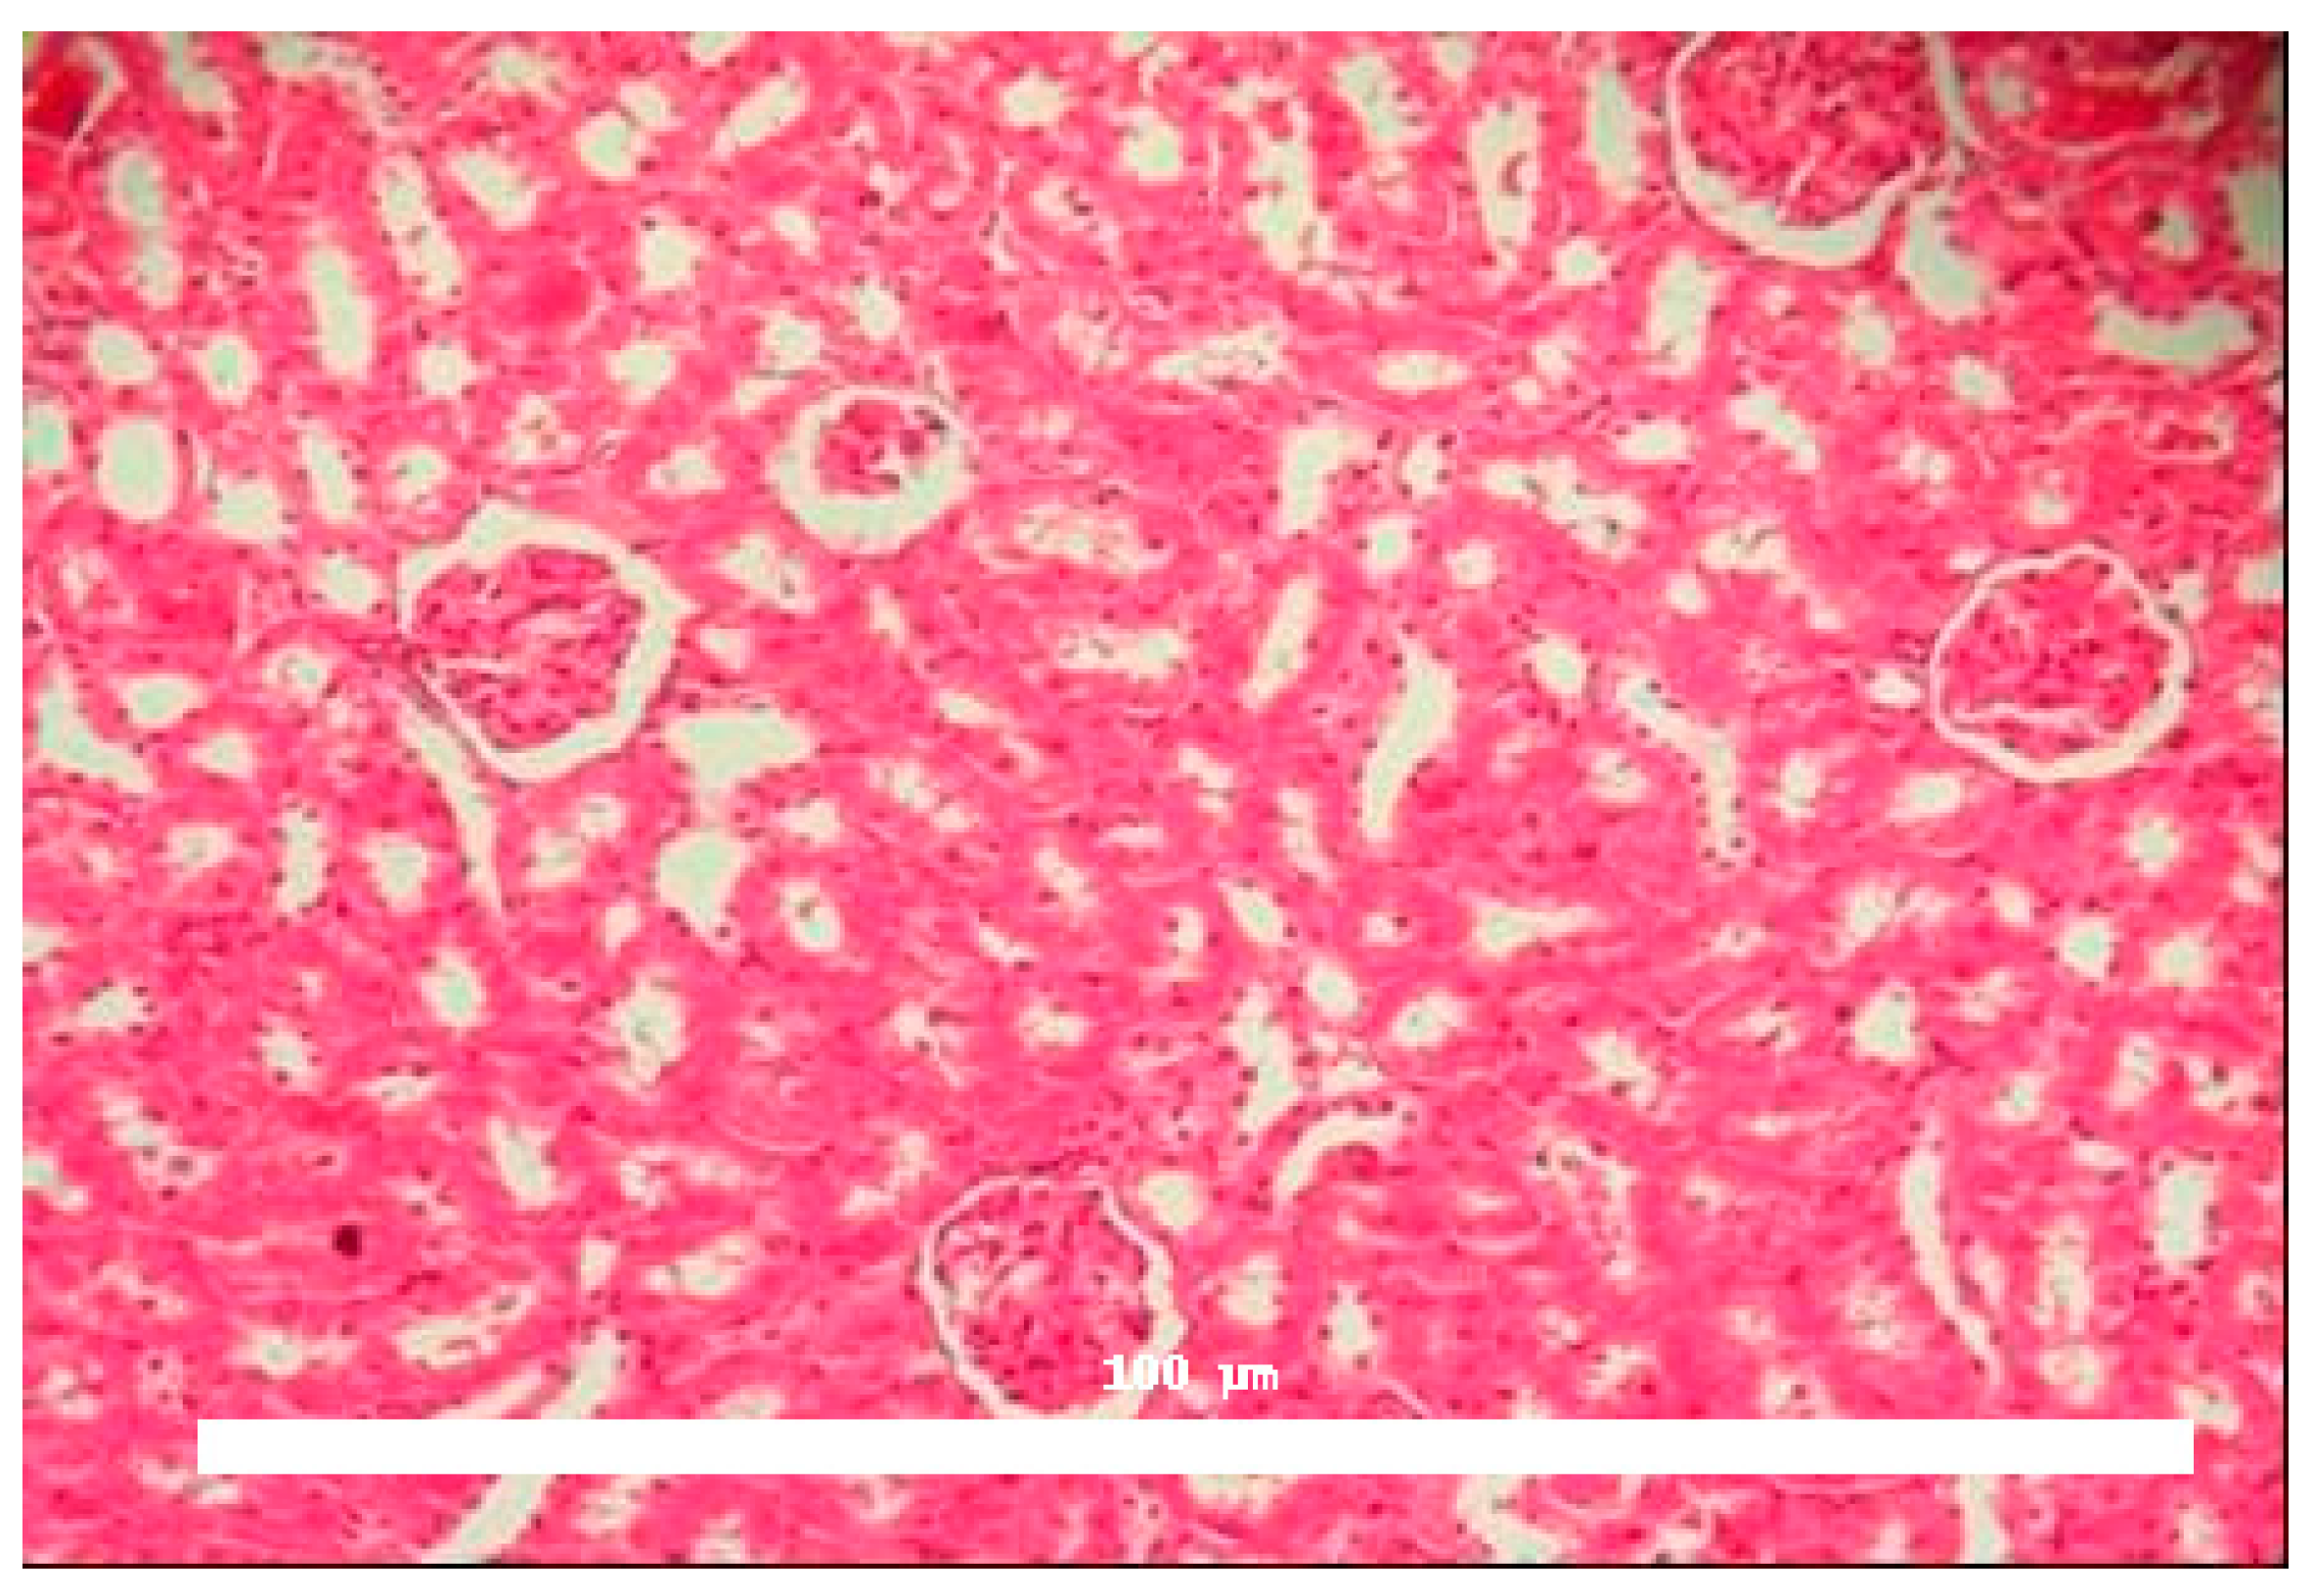

Significant morphological alterations were also observed. Figure 2 shows a histological section of a kidney perfused solely with Krebs–Henseleit solution, demonstrating no structural changes induced by the vehicle. The examined slides showed that glomeruli, tubules, vessels, and interstitial tissue appeared normal. In contrast, kidneys perfused with BaV displayed tubules containing a substantial amount of proteinaceous material (Figure 3).

Histological analysis confirmed discrete morphological changes in BaV-perfused kidneys, characterized by proteinaceous deposits in renal tubules, indicating possible glomerular or tubular damage. This finding aligns with the functional data and suggests structural consequences of venom exposure.

For histological evaluation, both kidneys (right and left) were fixed in formaldehyde and subsequently processed. Tissue fragments underwent dehydration, clearing, and sectioning into 3 µm slices. Hematoxylin-eosin (HE) staining was applied, and the samples were examined under a light microscope.

Figure 2. Histological evaluation of kidneys perfused with Krebs–Henseleit solution. No morphological alterations were identified in glomerular or tubular structures, and medullary tubules appeared normal in control samples. Magnification: 100×, hematoxylin and eosin staining.